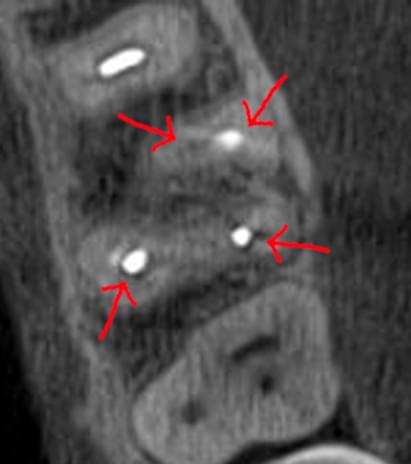

Зуб — це не просто монолітний об'єкт, а складна система мікроканалів. На плоскому 2D-знімку вони часто перекривають один одного, створюючи ілюзію простої анатомії.

Непомічений канал — це джерело майбутньої інфекції та причина «загадкового» болю після лікування. Завдяки високій роздільній здатності обладнання MyRay, лікар бачить кожен мікронний канал ще до того, як візьме до рук інструмент.